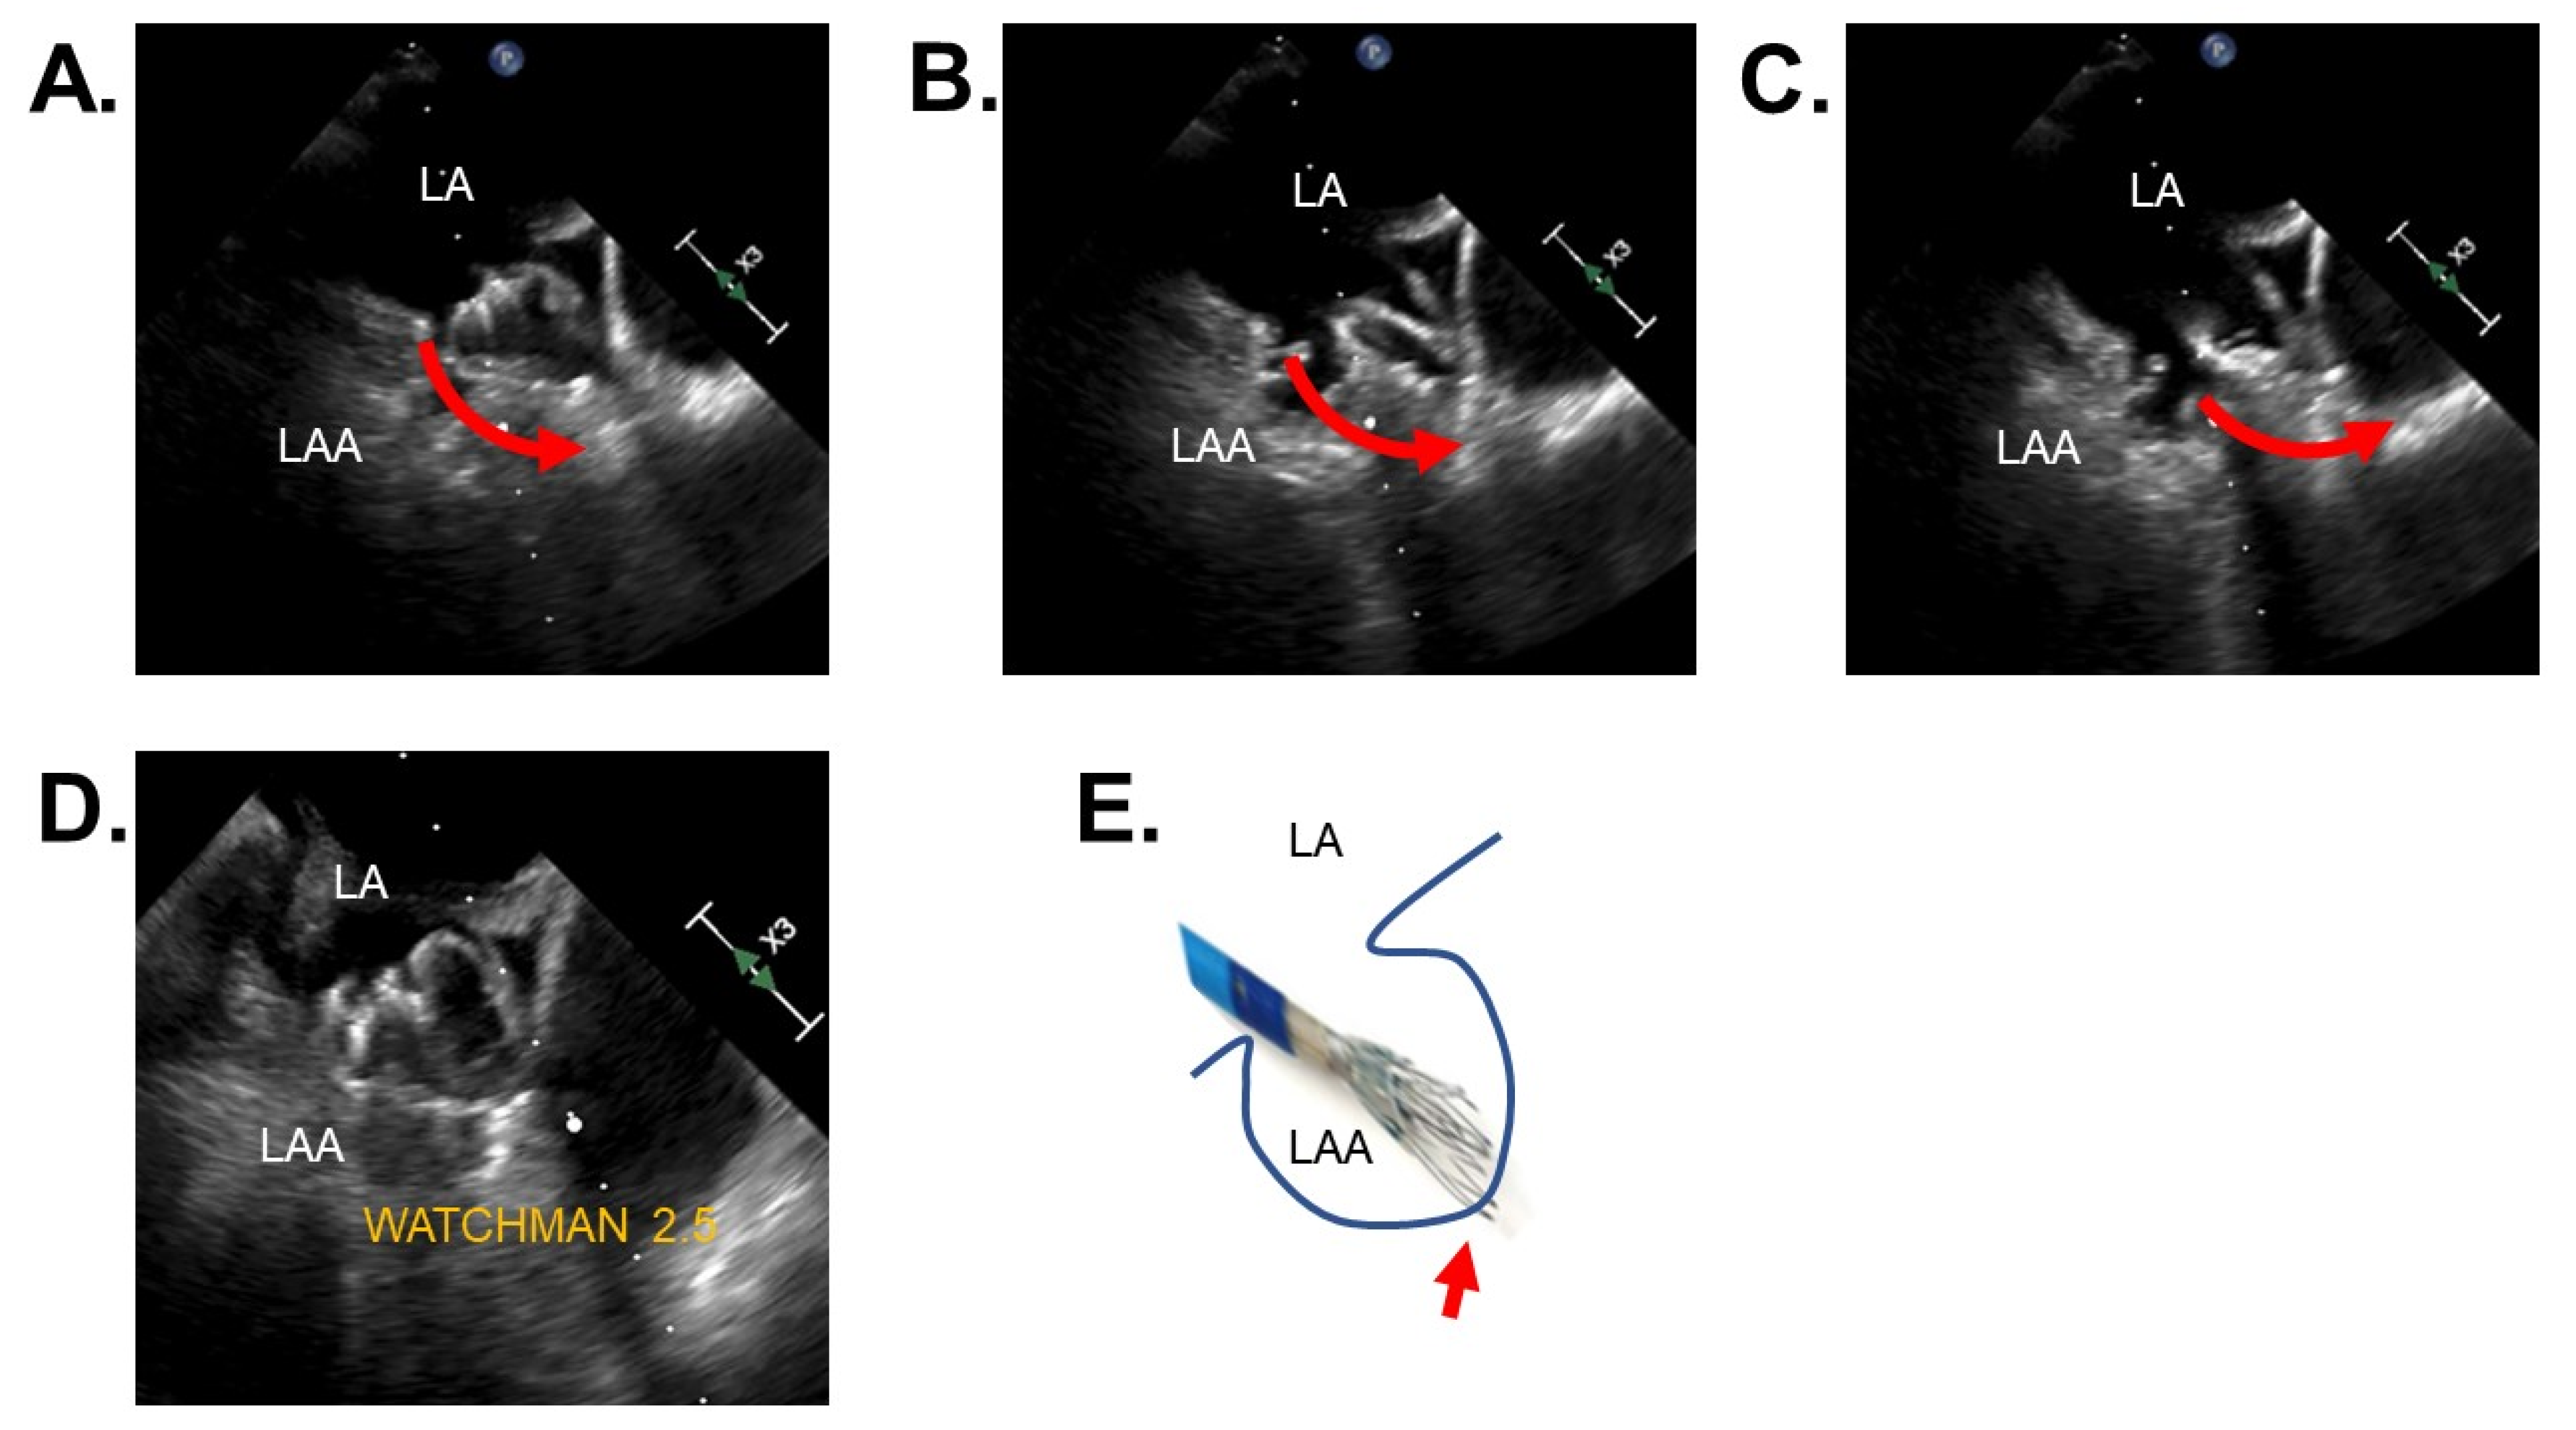

3.4. Clinical Events